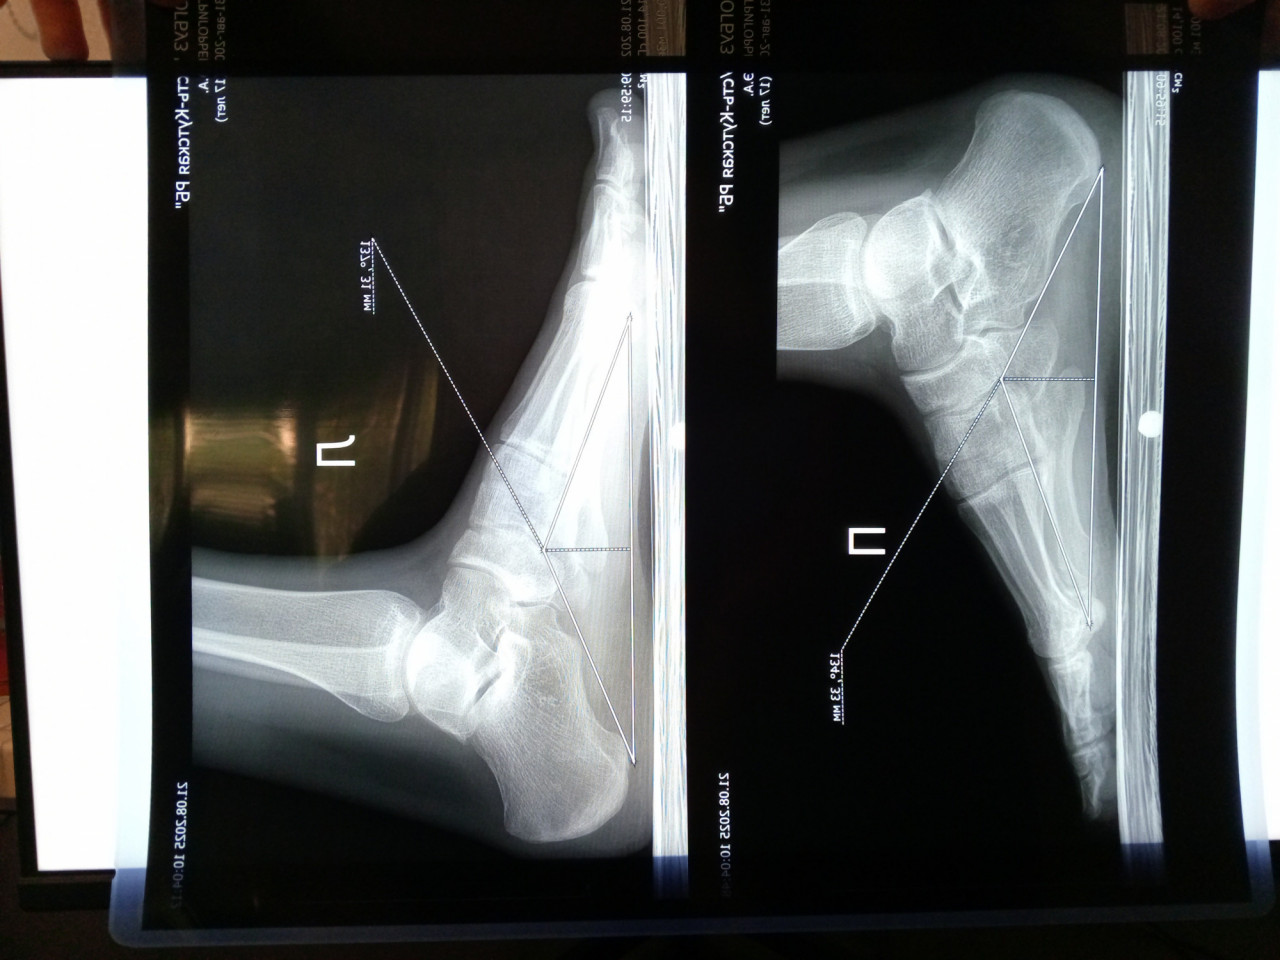

Здравствуйте. Сыну 17 лет. Были на приёме у ортопеда. Заключение после осмотра: эквино-плоско-вальгусная деформация стоп. Сделали рентген в двух проекциях: прямой без нагрузки и боковой с нагрузкой. В заключении написано плоскостопие 1ст. А про вальгус ничего. Из жалоб боли при ходьбе в области пяток в основном. Походка пружинящая, пятками еле касается пола. Посмотрите пожалуйста снимки, действительно у него плосковальгусная стопа? Или же нужно искать причину болей в другом?

Здравствуйте. По рентгену у вашего сына действительно отмечаются признаки плоскостопия 1 степени. Вальгусная деформация выражена слабо, поэтому в заключении её могли не указать. Боли в пятках и пружинящая походка могут быть связаны не только с плосковальгусной стопой, но и с перегрузкой ахиллова сухожилия или проблемами с пяткой. Рекомендую повторно показать ребёнка ортопеду, сделать УЗИ мягких тканей стопы и при необходимости дообследование, а также использовать индивидуальные ортопедические стельки.

Здравствуйте.  На снимках видно уплощение сводов стоп, что подтверждает плоскостопие начальной степени. Чёткой выраженной вальгусной деформации не прослеживается, поэтому в заключении её могли не отметить. Однако жалобы на боли в пятках требуют дообследования и стоит исключить воспаление подошвенной фасции или перегрузку зоны роста пяточной кости. Рекомендую обратиться к ортопеду для подбора ортопедической обуви или стелек, ограничить длительные нагрузки и по показаниям пройти физиотерапию.